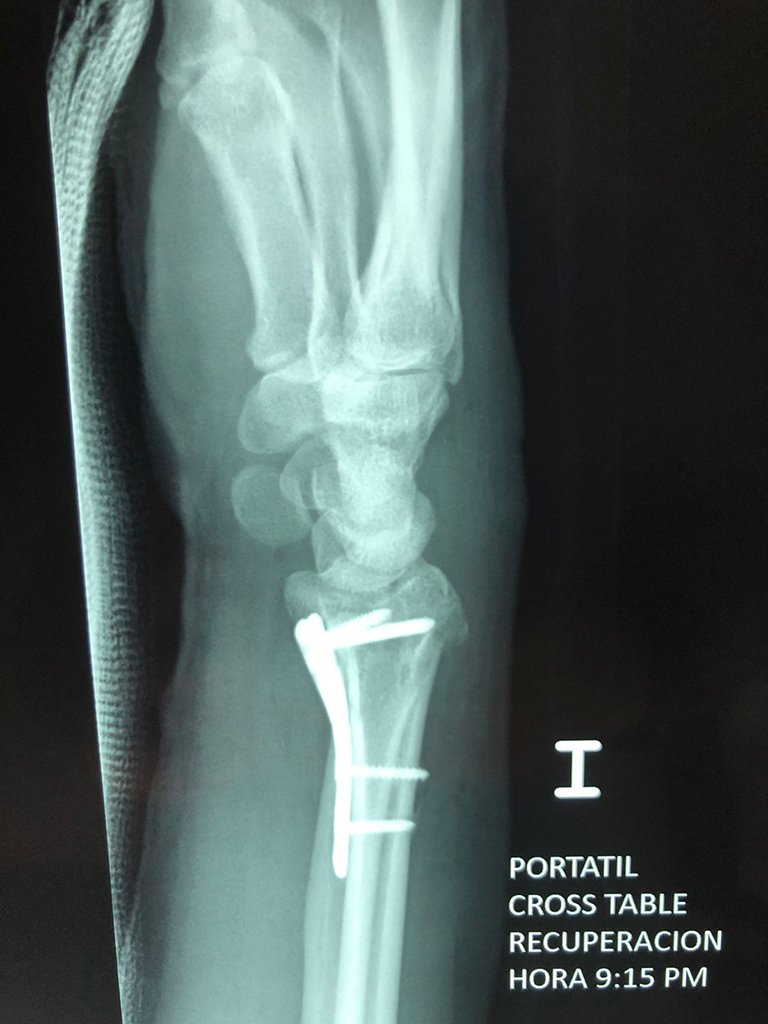

Calcaneo - Cirugías de Muñecas y Manos

Los procedimientos más comunes en cirugía de la mano son aquellos destinados a reparar traumatismos, incluyendo lesiones de tendones, nervios, vasos sanguíneos, y articulaciones; huesos fracturados; y quemaduras, cortes, y otros daños de la piel.